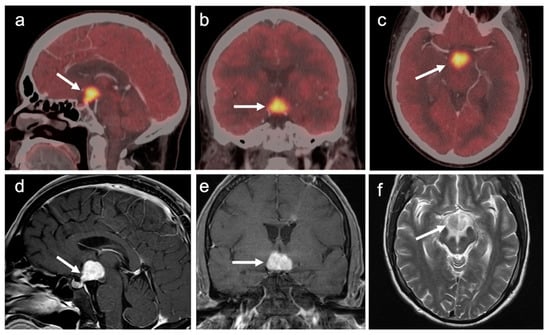

3.4. CNS Lymphoma

3.5. Brain Metastases

3.6. Response to Therapy